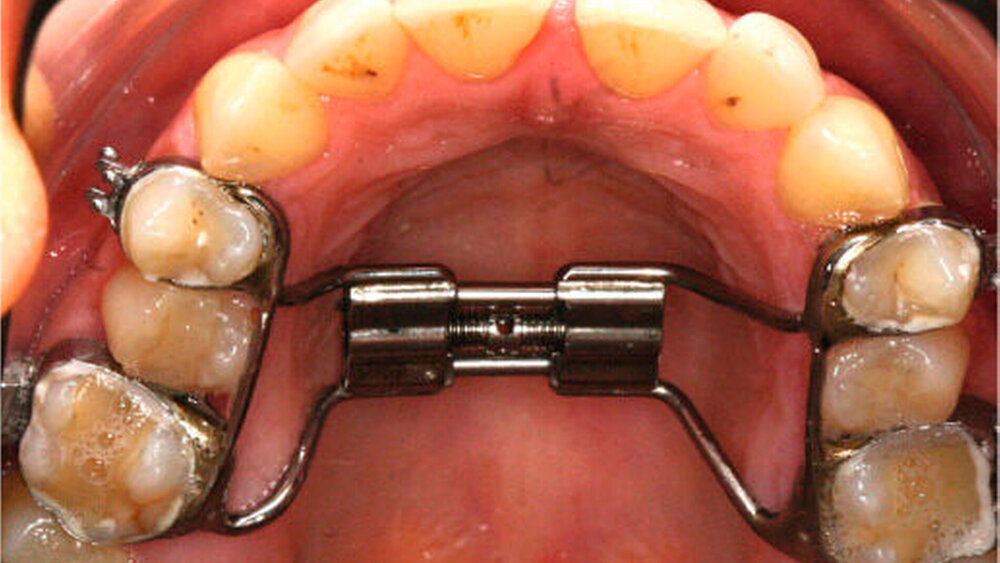

Anfangs wurde bei der Patientin eine transversale Expansion von etwa 5 mm mittels konventioneller GNE (Abbildung 3a) durchgeführt. Nach sechsmonatiger Retention durch Belassen der GNE-Apparatur konnte die individualisierte linguale Apparatur (Incognito, 3M Unitek, TOP-Service für Lingualtechnik GmbH, Bad Essen) eingesetzt werden (Abbildung 3b).